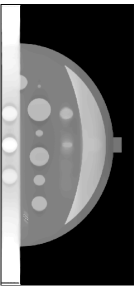

II Breast Phantom

A breast phantom was designed to provide a basis for algorithm comparison. It consists of objects with different geometric shapes to allow for analytic computation of the projection data. The overall shape of the compressed breast of 50 mm thickness is modeled by a truncated ellipsoid. Attenuation coefficients at a photon energy of 30 keV [10] were used for phantom materials simulating the fibroglandular, tumour and muscle tissues, as well as microcalcifications in the breast. In Fig. 1, we display the phantom images within 2D planes specified by (a) mm, by (b) mm, (c) mm, and (d) mm, respectively. As shown in Fig. 1a, the crescent-shaped region, representing the fibroglandular tissue region of the breast, is attached to a rectangular slab of higher attenuation, simulating the pectoralis muscle. It can be observed in Fig. 1 that numerous test objects of different sizes and contrast levels are embedded in the phantom for simulating mass lesions and microcalcifications. In particular, a row of three ellipsoids is embedded in the pectoralis muscle (see Fig. 1(b)), with equal in-plane diameters but varying flatness, thus allowing one to evaluate whether shapes of equal in-plane profile, but different in-depth profiles, can be resolved. Furthermore, six spheres of different diameters, ranging from 5 mm to 15 mm, are equally distributed in the fatty area of the breast (see Fig. 1(c)). It can also be observed in Fig. 1(d) that three pairs of stacked spheres of identical diameter mm are embedded in the breast region with different spacings of , , and , respectively, for these pairs. Finally, two clusters of small spheres of diameters 0.3 mm and 0.15 mm are included to model microcalcifications.